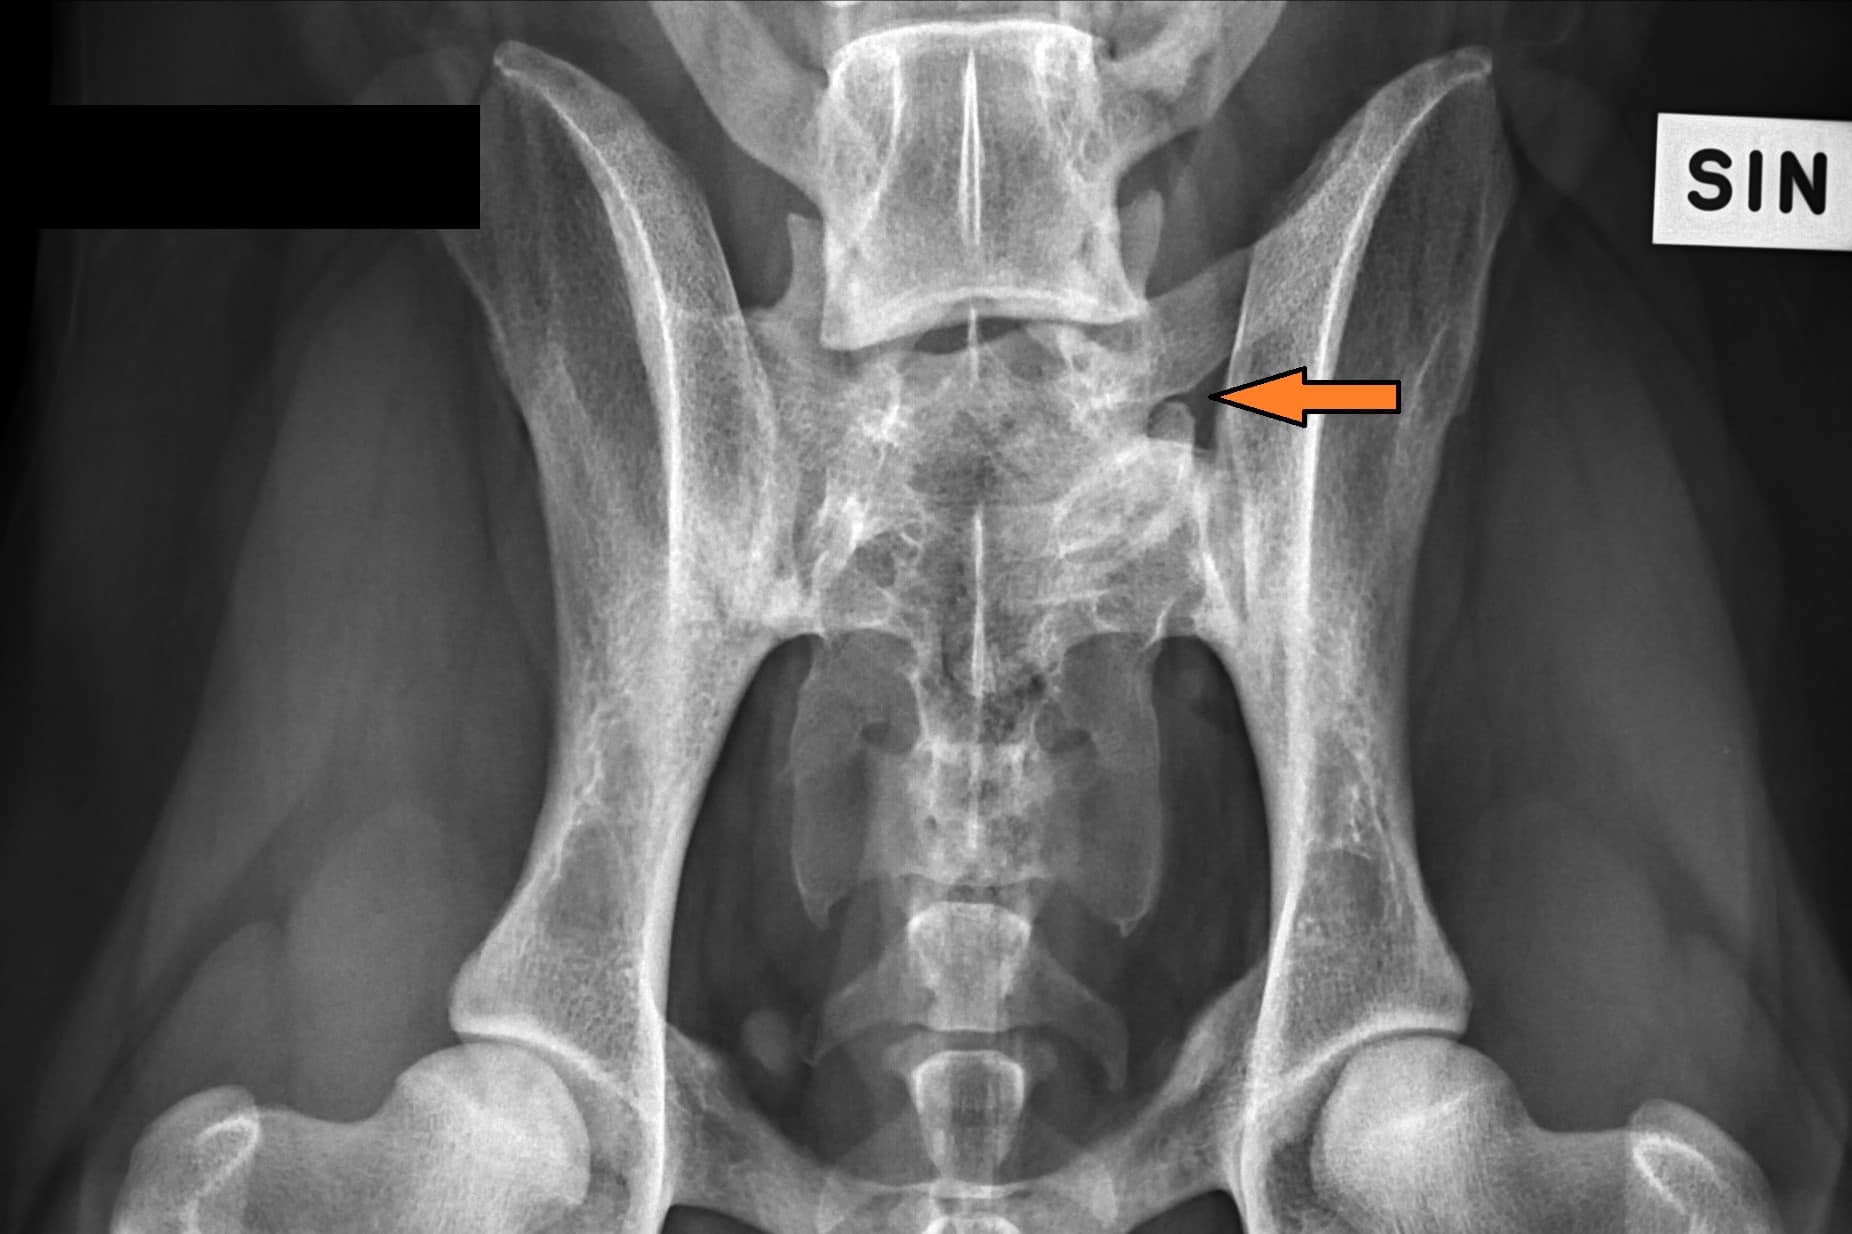

LTV2; symmetrical

LTV3; asymmetrical; on the right in the VD photo the left side of S1 is shaped like a sacral vertebra and on the right side S1 is shaped like a lumbar vertebra including the spinous process.

The asymmetrical form, LTV3, seems to be a bit more tricky than the other forms. In some cases asymmetrical form comes with rotated pelvis, which might lead to unilateral development in hips. This is actually very logical; when the pelvis is not straight and in balance there will be uneven bear of weight between hips. In long term this uneven state might cause the worse hip wear sooner than the better hip and lameness and osteoarthritis may occur.

In the Finnish Kennel Club’s database 38,9% of Rhodesian Ridgebacks with LTV3 have one hip scored 1-2 degrees lower than the other one, ie. A/C (Oct 2020). The score doesn’t tell if the dog’s pelvis is straight or rotated.

“Asymmetrical LTV favours pelvic rotation over its long axis, resulting in inadequate femoral head coverage by the acetabulum on one side. Inadequate coverage of the femoral head favours subluxation, malformation of the hip joint, and secondary osteoarthritis. Asymmetrical hip conformation may therefore be the sequela of a LTV and mask or aggravate genetically induced canine hip dysplasia.”

(Flückiger M., Frank Steffen F. et al 2017)